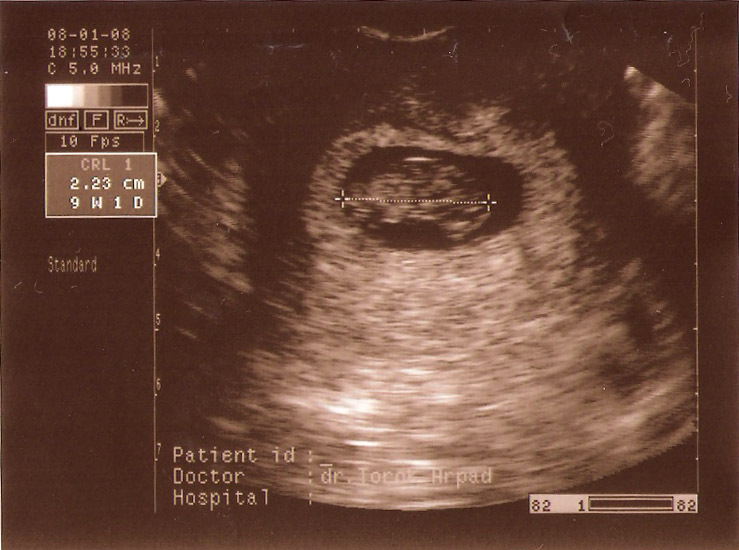

A fejlődés fokozatai:

9 hetes UH-ról két fotó:

12 hetes UH-ról videó.

16 hetes UH-ról videó.

Hihetetlen, hogy nő... És lassan már 19 hetes...